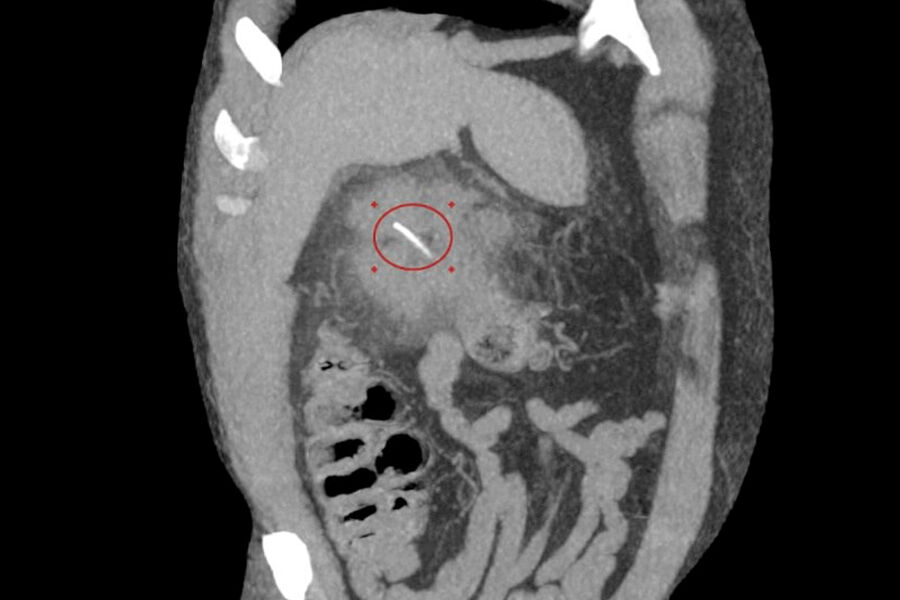

Врачи Луховицкой больницы спасли 64-летнего мужчину, у которого кость проткнула кишечник и вызвала гнойное воспаление. Об этом сообщили в пресс-службе Минздрава Московской области.

Во время обследования медики увидели, что трехсантиметровая кость застряла в толстом кишечнике и проделала в нем отверстие. В этом месте началось гнойное воспаление.

«Мы провели КТ-диагностику, после чего вскрыли абсцесс под спинальной анестезией и удалили гной. Операция прошла успешно», — поделился хирург больницы Илья Луньков.